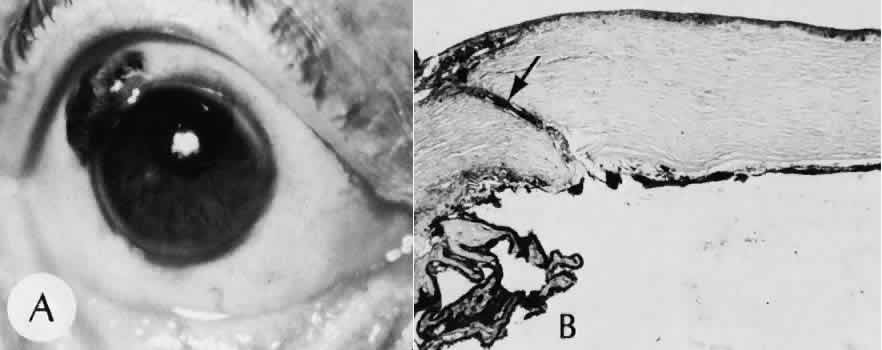

| Successful wound healing in the eye is a precise, ordered series of events